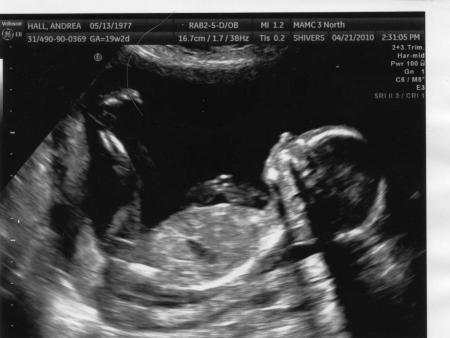

Und dann noch das Geschlechtsbestimmungs-Bild, was wir bekommen haben. Ich kann ja darauf so rein GAR nix erkennen, hab aber auch noch vorher nie so ein Bild gesehen gehabt. Die Dame, die den Ultraschall gemacht hat, war sich aber doch recht sicher, dass es 'girl parts' sind, dass wir also ein Maedchen bekommen.

Bild zu

Deine Bilder sind echt süß, besonders das erste!! Also ich kann auf diesen Bildern auch nie so recht was erkennen, auf deinem Girl-Bild kann ich nichts erkennen, was auf Mädchen hinweist- aber die Ärztin wirds wohl wissen!!!! Ansonsten sieht` so aus, als würde deine Kleine eine süße Stupsnase haben - total süß VG

Ja, Sandra... bei dir sieht man das mit dem Jungen eindeutig. ;-) Ich kann immerhin mittlerweile schon erkennen, dass das Bild von uns im gleichen Winkel aufgenommen wurde. Am Anfang wusste ich ja noch nicht mal, von wo ich da auf was draufschaue... aber mittlerweile hab ich andere 'Beweisbilder' gesehen und da sieht's dann doch bei uns schon eher so aus wie ein Maedel.